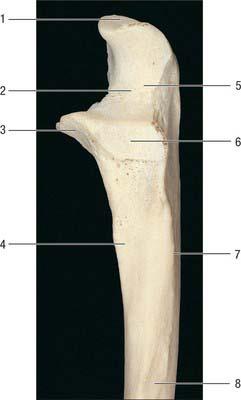

9. Number 2 refers to:

Explanation

Number 2 refers to the facet for the articular part of the tubercle of the rib. This means that it is a specific feature or surface on a bone that is involved in the articulation or joint formation with the tubercle of a rib.

Number 2 refers to: